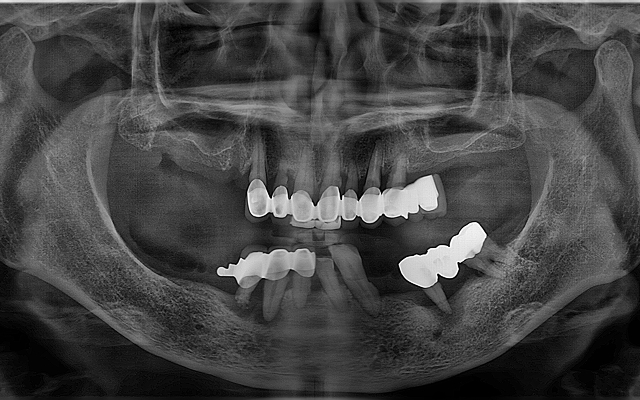

고난도 뼈이식 케이스

- 정밀 영상 진단으로 결손 부위를 파악하여 안전하게 골이식

- 미세 수술 장비를 활용해 식립 안정성 및 성공률 향상